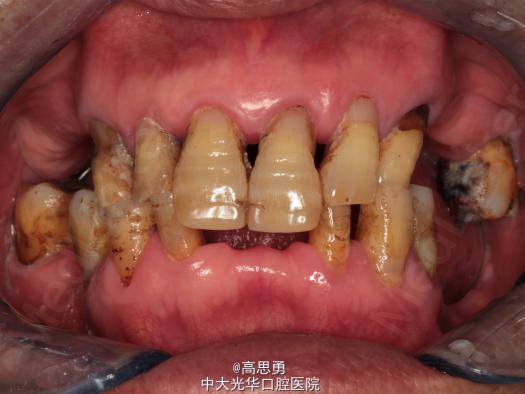

5、口内检查:

#32近中移位约1mm,无明显倾斜

#44远中移位约2mm,向缺隙侧倾斜,伸长约1mm

其余缺牙间隙正常

全口牙龈退缩至根颈1/3,牙龈无肿胀无瘘管

上颌缺牙区牙槽嵴无明显吸收、下颌缺牙区牙槽嵴吸收呈低平刃状

口腔卫生状况欠佳、全口牙石多

11 12 13 14 15 16 17 21 22 23 24 25 26 27

视 存 存 存 缺 缺 缺 缺 存 存 存 缺 缺 缺 存

探 - - + - - - - - - - - - - -

叩 - - + - - - - - - - - - - -

松 - - I° - - - - - - - - - - -

楔 O O O - - - - O O O - - - -

31 32 33 34 35 36 37 41 42 43 44 45 46 47

视 缺 存 存 存 缺 缺 缺 缺 存 存 存 缺 缺 存

探 - - - - - - - - - - - - - -

叩 - - - - - - - - - - - - - -

松 - - - - - - - - - - - - - -

楔 - - O - - - - - O O O - - -

根尖X片示:13 根尖部阴影,牙颈部硬组织部分缺损